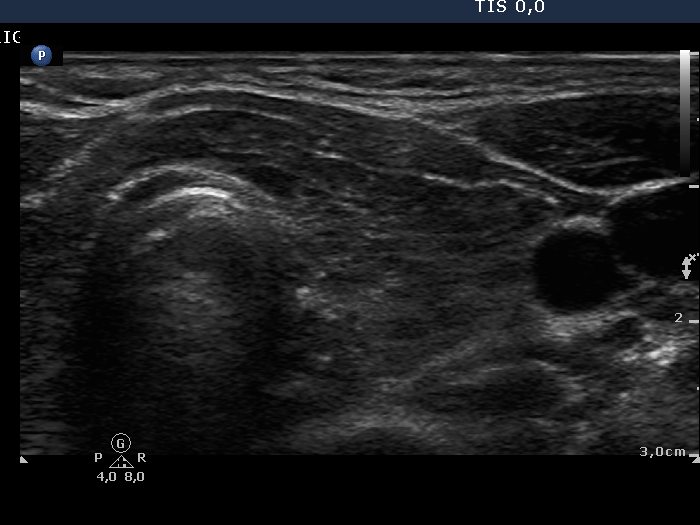

Chronic lymphocytic thyroiditis - Case 2. |

Ultrasonography: both thyroids were hypoechogenic with fibrotic changes. Based on the previously described "nodule", the fibrotic changes were more pronounced. This area did not fit a nodule.

FNAC disclosed Hashimoto's thyroiditis.